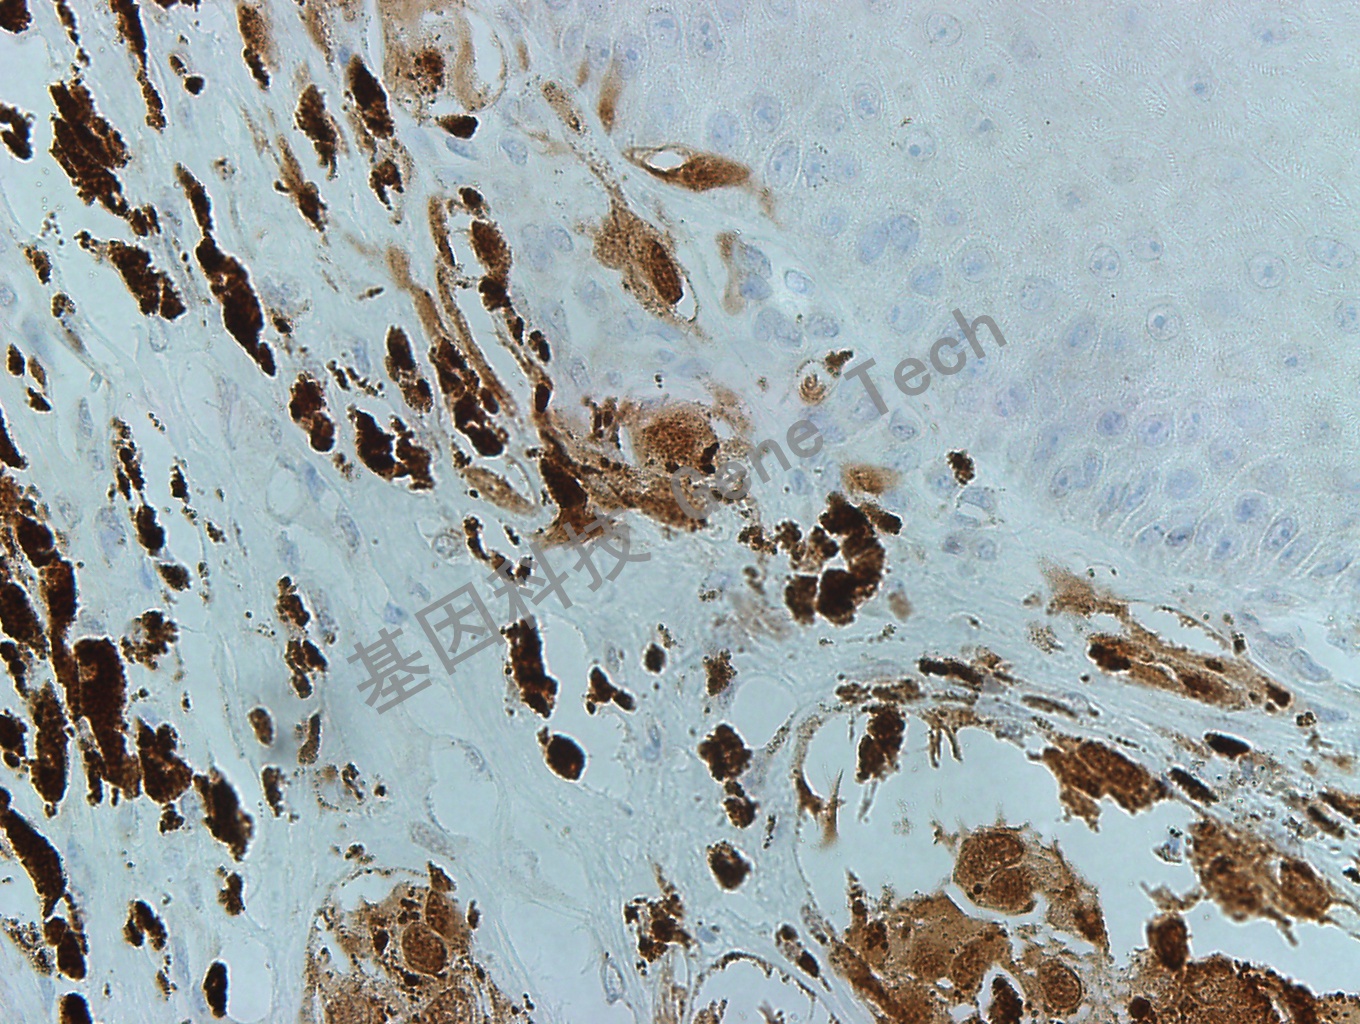

MITF GT2263 黑色素瘤10X_副本.jpg黑色素瘤石蜡切片,用 MITF(GT2263)染色,细胞核阳性,DAB 显色。

MITF GT2263 黑色素瘤40X_副本.jpg黑色素瘤石蜡切片,用 MITF(GT2263)染色,细胞核阳性,DAB 显色。

MITF GT2263 黑色素瘤40X-2_副本.jpg黑色素瘤石蜡切片,用 MITF(GT2263)染色,细胞核阳性,DAB 显色。